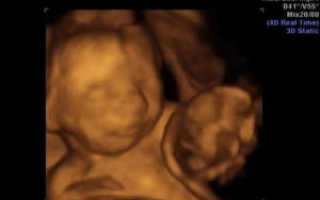

Рост и развитие плодов: На 22-й неделе беременности двойней оба плода продолжают активно расти. Каждый из них может достигать длины около 27 см и весить около 500-600 граммов. В этот период они начинают развивать свои уникальные черты лица, а также активно двигаются, что может быть заметно маме.

Риски и наблюдение: Беременность двойней может быть связана с повышенными рисками, такими как преждевременные роды и преэклампсия. Поэтому на 22-й неделе важно проходить регулярные обследования и следить за состоянием здоровья как матери, так и плодов. Врачи могут рекомендовать дополнительные УЗИ и мониторинг для обеспечения безопасности обоих детей.